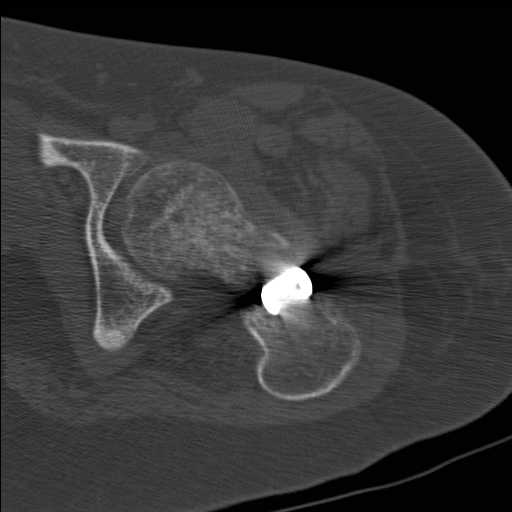

Перелом шейки бедра у девушки 19 лет. Чем лучше помочь?

Добрый день уважаемые коллеги. Во такая ситуация. Девушка 19 лет травму

получила в мае 2016г( изолированная травма, трансцервикальный перелом

шейки левого бедра). Соматически здорова. Лечилась по месту жительства

скелетным вытяжением в течении 1 месяца. Затем переведена в наше

учреждение. 18 июня выполнена операция, детали где , кто и как уточнять

не имеет смысла( из протокола операции: выполнялась передняя артротомия,

репозиция под визуальным контролем) . Учитывая характер выполненного

остеосинтеза, после операции постельный режим 6 недель. Снимки в

хронологии все выкладываю. КТ контроль сделан 2.09.16.  для оценки

состояния  головки бедра. Помогите, определиться с дальнейшей тактикой.